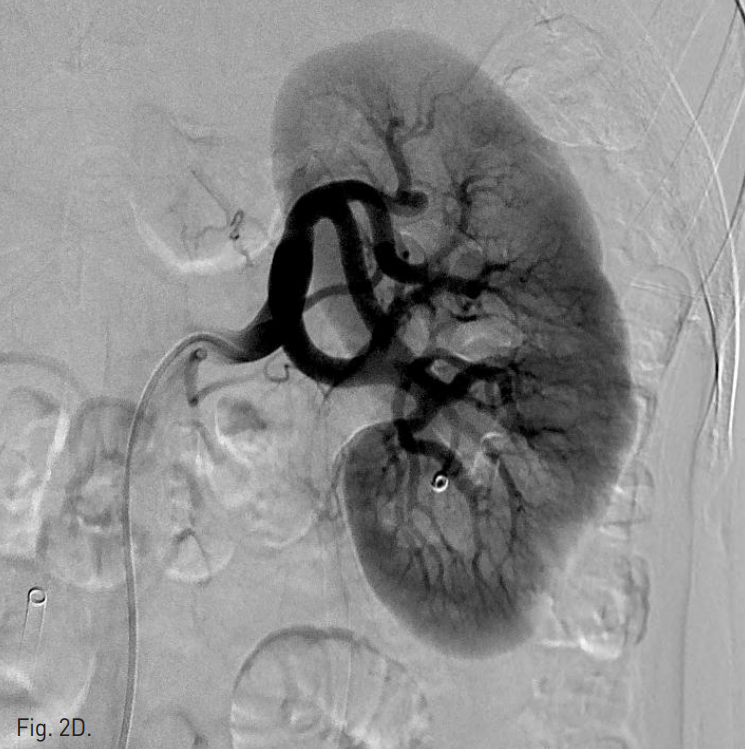

이어 환자를 복와위로 돌려눕히고, 초음파 유도하에 21G Chiba needle로 nidus를 직접 천자 후 혈관조영술을 시행하여 동정맥기 형의 nidus와 유출정맥을 확인하였다(Fig. 2B). Chiba needle을 통하여 3mm × 2cm Tornado coil(Cook, Bloomington, IN)을 nidus에 넣자 유출정맥의 기시부가 매우 좁아서 유출정맥의 입구에 걸려 혈류가 느려졌다. 이후 Gelfoam을 소량 주입하여 혈류가 거의 없어짐을 확인한 뒤, Chiba needle을 nidus의 가장 깊은 위치에서부터 후진시키며, 99% 알코올을 소량씩 주입하여 색전을 시행하였다(Fig. 2C). 색전술 후 시행한 왼쪽 신장동맥 혈관조영술에서 동정맥기형은 더 이상 관찰되지 않는다(Fig. 2D).

Fig. 2

D. Post-embolization angiogram shows complete embolization of the renal AVM.